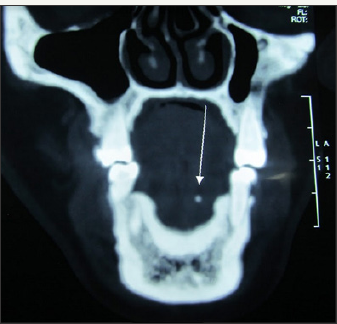

A 58 year old female reported with a chief complaint of intermittent swelling in left submandibular region. The swelling was related to meals and persisted for 2-3 hours after food. It was variable in size and occurrence. On examination, there was mild swelling in submandibular region (Figure 1). Ductal orifice was slightly reddish and tender signifying inflammation. Expressed saliva was normal in appearance and consistency but the salivary flow was relatively reduced compared to contra lateral side. Clinical diagnosis of left submandibular sialolith was made. A computerised tomogram revealed a 2.4mm radiopaque mass in anterior part of the left Wharton's duct (Figure 2a-2c). However, the calculus was not visible or palpable. The sialolith was removed intra orally under local anesthesia. The surgical technique has already been discussed (Figure 3-7).

Figure 2b: Coronal section of CT showing sialolith.